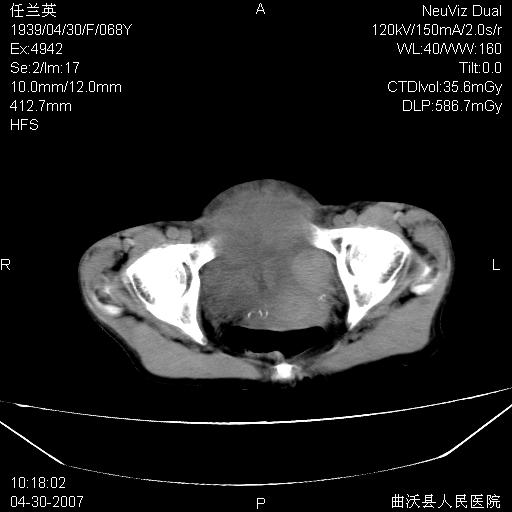

患者,女,68岁,感觉腹部憋涨发硬数天,查b超发现左盆腔有囊性肿物和少量腹水,行ct检查

1.考虑卵巢肿瘤并腹腔广泛性转移可能性大;

2.腹盆腔少量积液。

难的一见 典型 - 网膜饼  冰冻骨盆 可以当教学片了